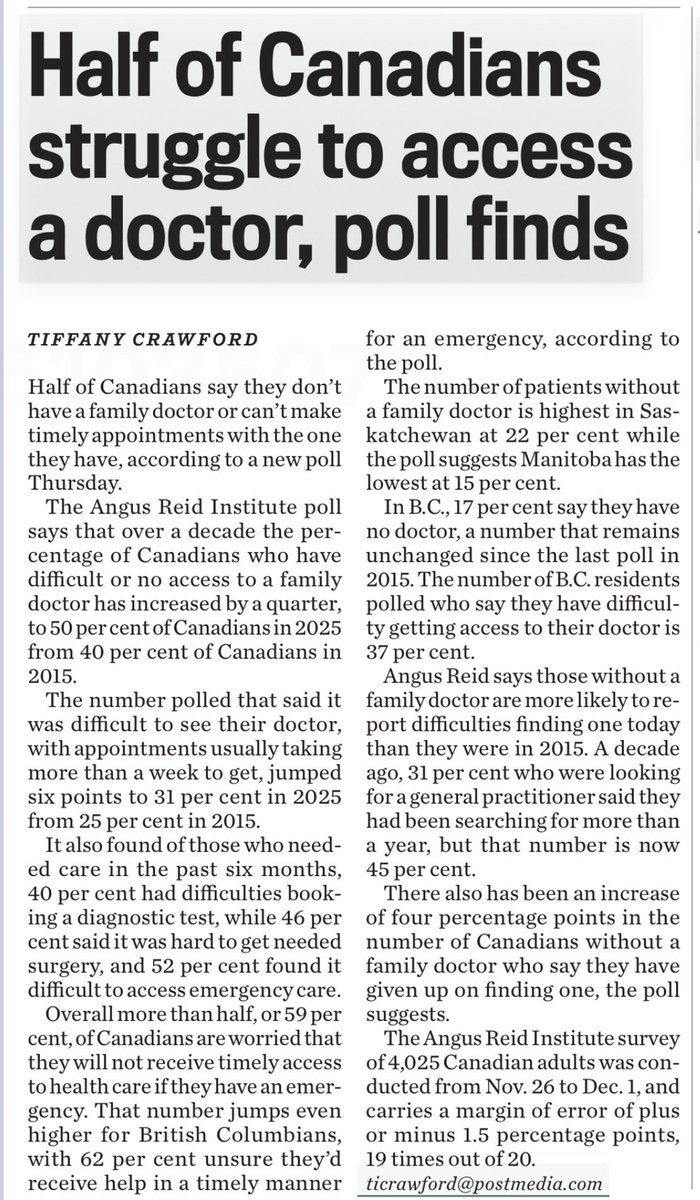

So sad that our system is failing young Canadians: Pediatric clinic closing at VGH, physicians say they are overwhelmed by demand timescolonist.com/local-news/ped… via Times Colonist